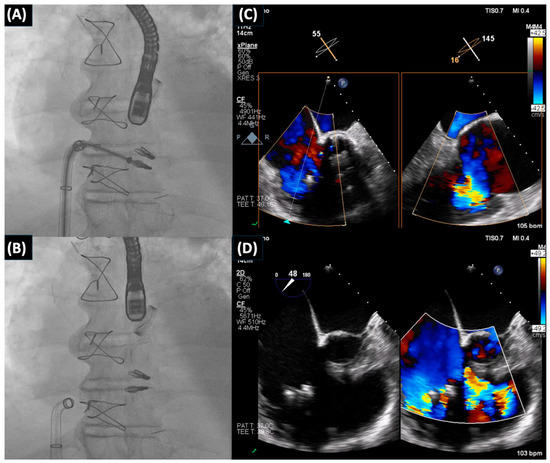

- Scotti, A.; Curio, J.; Leone, P.P.; Ludwig, S.; Coisne, A.; Sturla, M.; Murthy, S.; Chau, M.; Granada, J.F.; Jorde, U.P.; et al. Management of Volume Overload in Severe Atrial-Functional Tricuspid Regurgitation: Improved Feasibility of Transcatheter Edge-to-Edge Repair. JACC Case Rep. 2023, 12, 101776. [Google Scholar] [CrossRef] [PubMed]